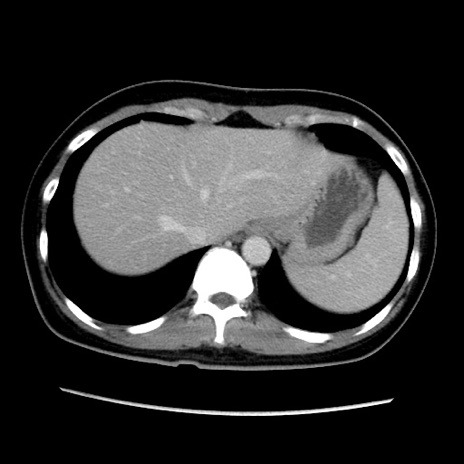

症例39(横断像)

【症例】40歳代女性

【主訴】上下腹部痛

【現病歴】2日目から下腹部痛あり。夜間は痛みで眠れなかった。昨日より上腹部痛と下痢が出現。臥位で痛みは軽快したため、休んでいた。本日になって臥位でも立位でも痛みが強くなってきたため救急要請。

【既往歴】子宮内膜症

【身体所見】部:平坦・軟、左上下腹部に圧痛あり、反跳痛あり。

【データ】WBC 21800、CRP 26.78